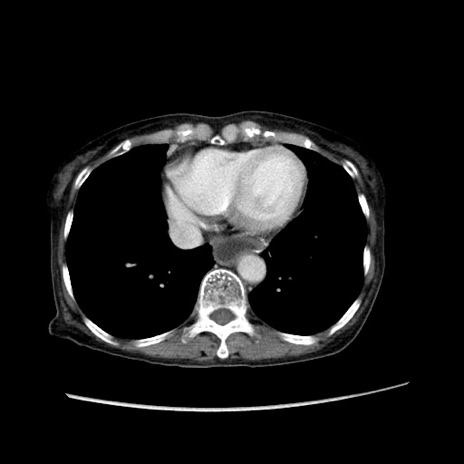

冠状断像

【症例】80歳代女性

【主訴】胸のつかえ感

【現病歴】約9時間前に食後から胸のつかえた感じあり、嘔吐あり、来院。

【既往歴】胃癌(全摘)、胆摘、虫垂炎

【身体所見】心窩部に圧痛あり、反跳痛なし。

【データ】WBC 5700、CRP 0.05